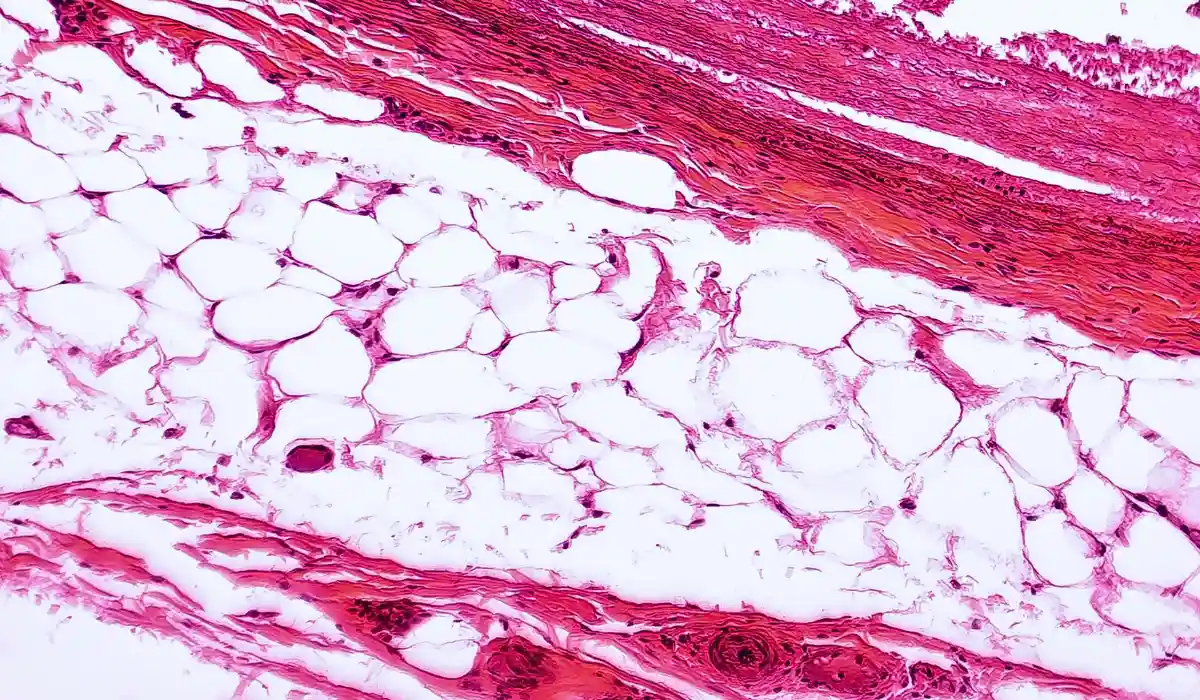

Adipose tissues also called body fat, are a type of connective tissue that extends throughout the body. These tissues can be found under the skin, between internal organs, and in the inner cavities of bones. It produces crucial hormones like leptin and adiponectin that influence hunger, fat burning, glucose metabolism, and where the body deposits fat.

Adipose tissue constitutes about 80 percent fat and the rest 20 percent includes other tissues. The tissue performs several important functions regarding the regulation of the whole body’s health.

There are two types of adipose tissues- subcutaneous and visceral tissues. The adipose tissue seen beneath the skin is referred to as subcutaneous tissue, while the one that lines the internal organs is referred to as visceral tissue.

Too much visceral adipose tissue can cause belly fat that push out of the belly. Therefore, in a way having too little subcutaneous fat decreases the padding and protection in the abdomen, allowing visceral abdominal fat to accumulate more readily around the organs when excess calories are consumed.